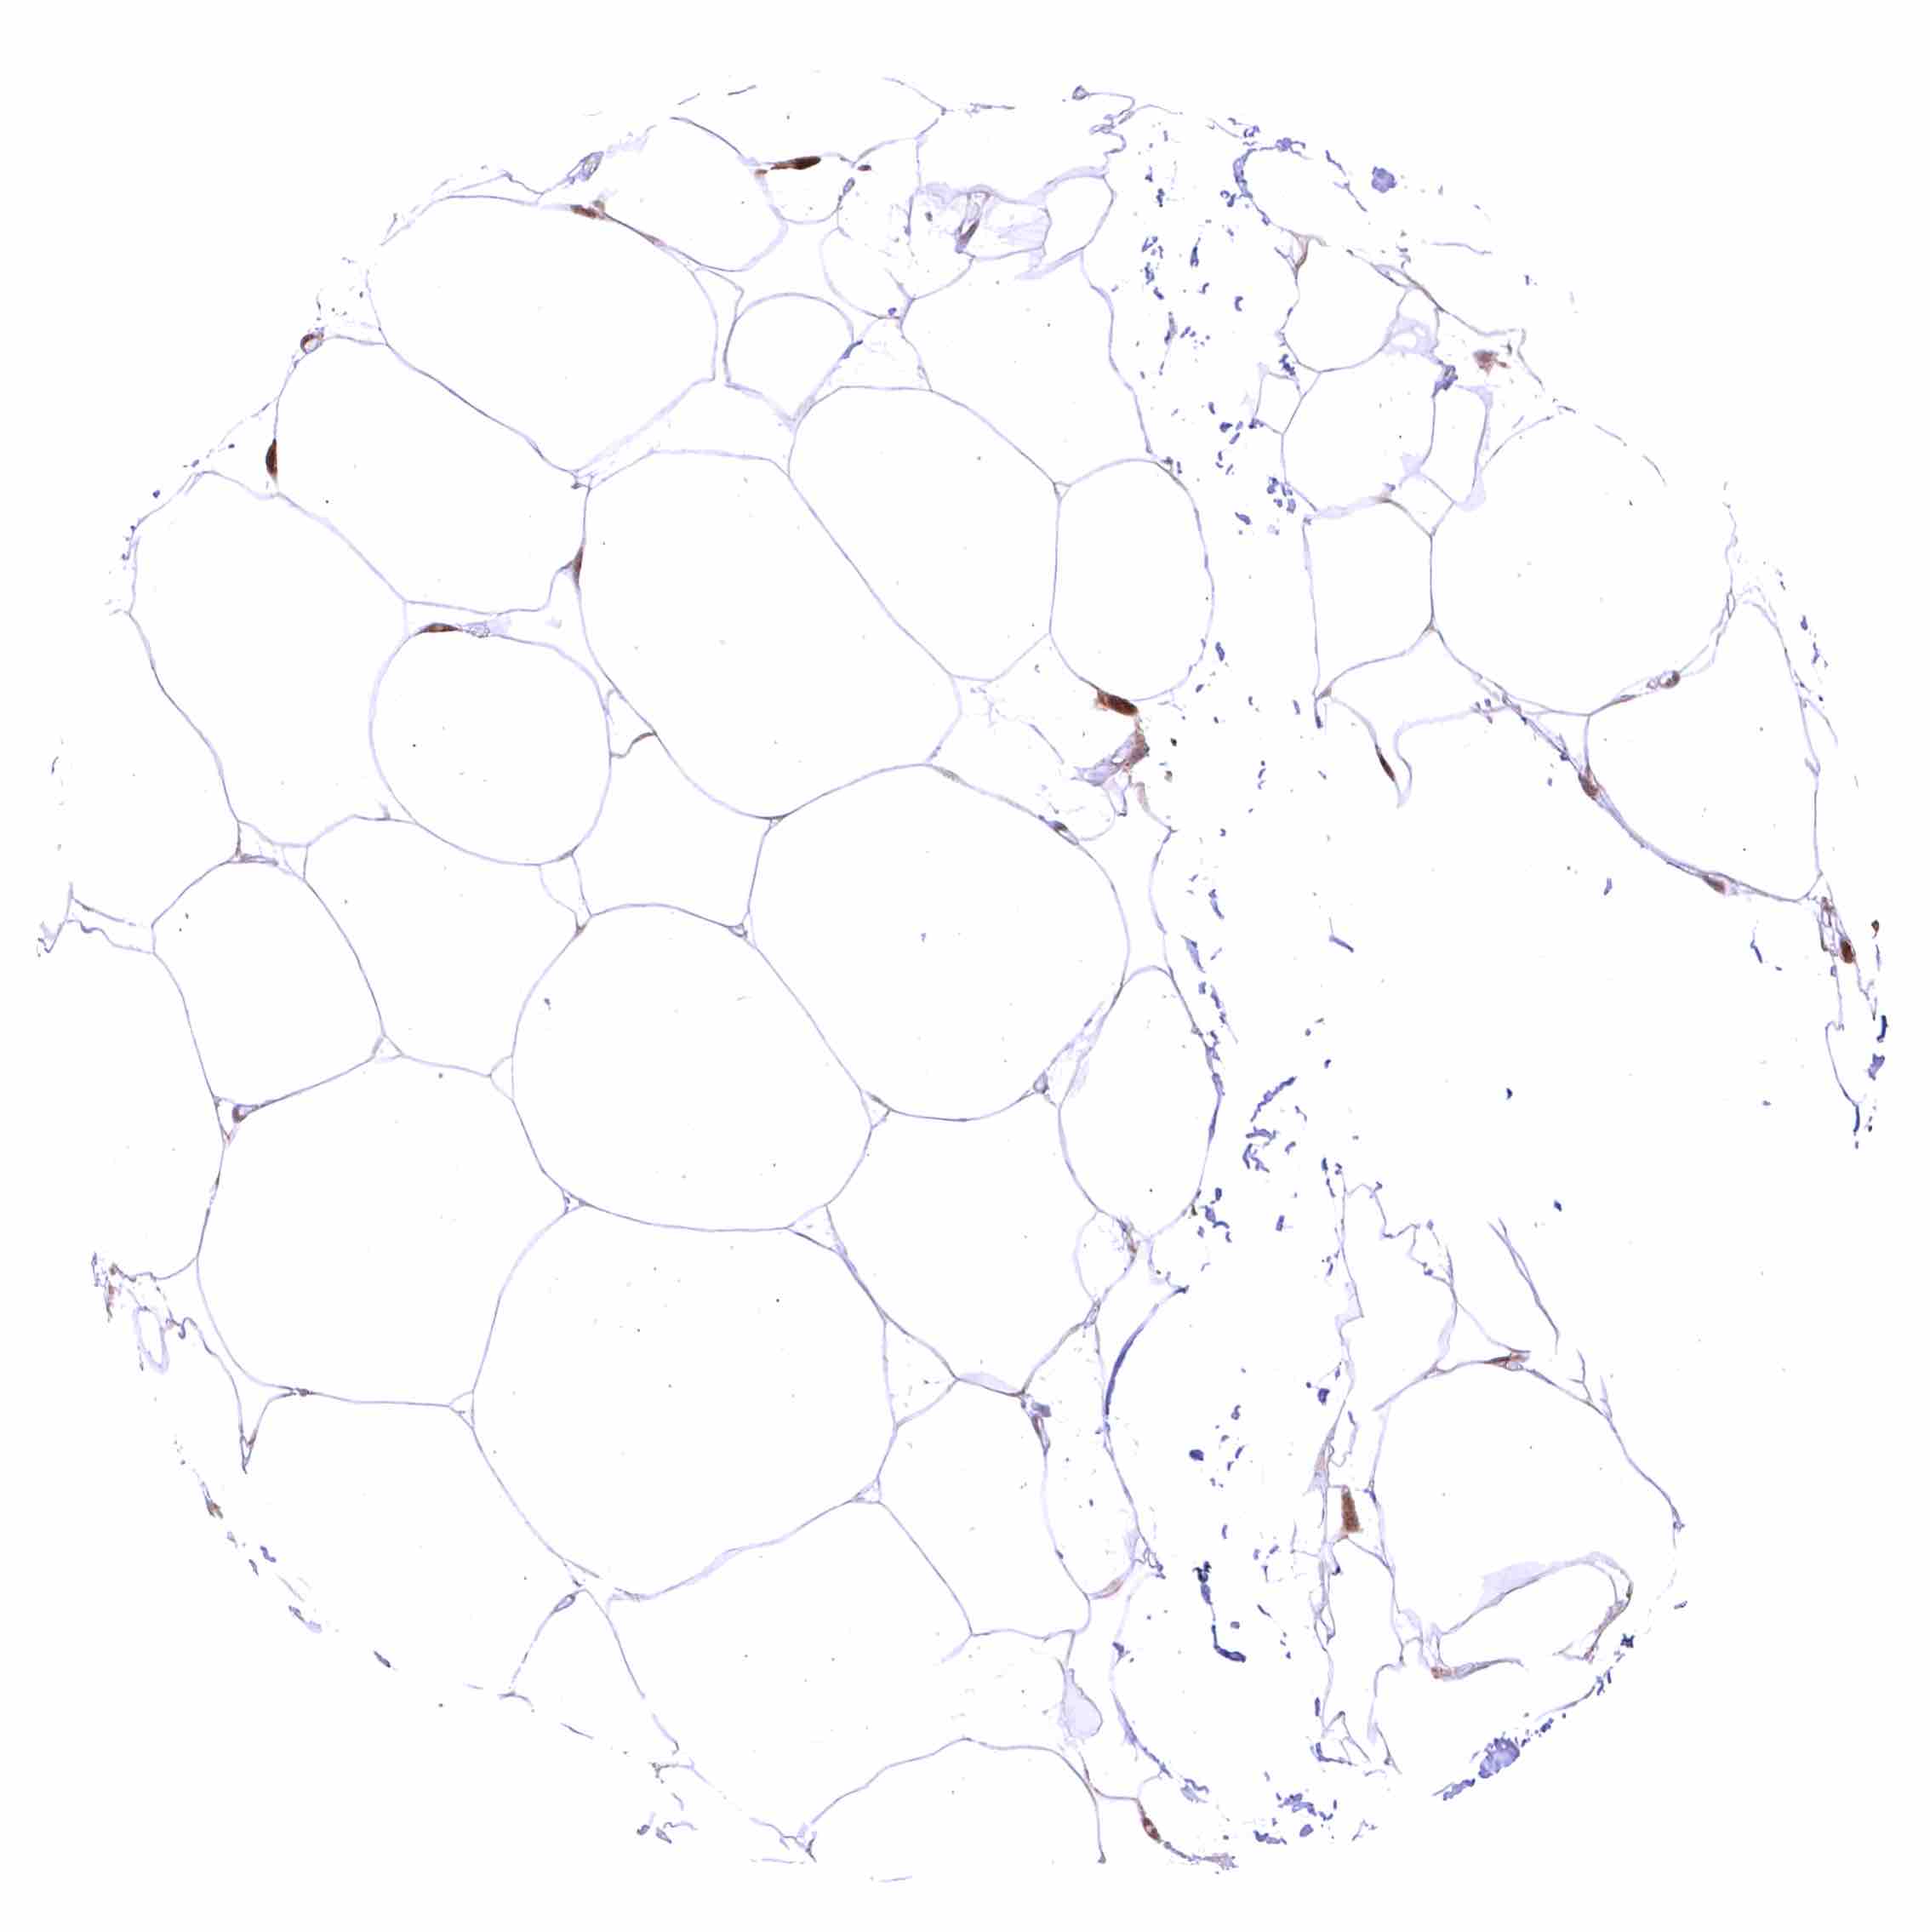

Fat